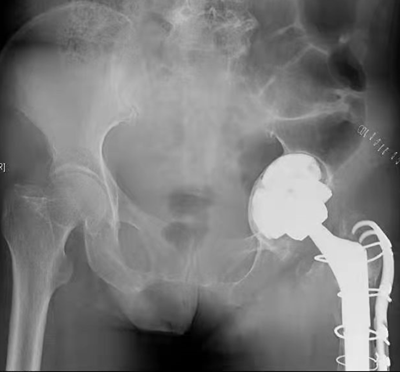

一位骨肿瘤患者手术“零输血”的背后

2021年6月14日是第18个世界献血者日,世界卫生组织发布活动口号“献血,让世界继续跳动”。 安全血液和血液制品及其输注是保健和公共卫生的一个重要方面。它们每天可以拯救数百万人的生命,改善许多患者的健康状况和...